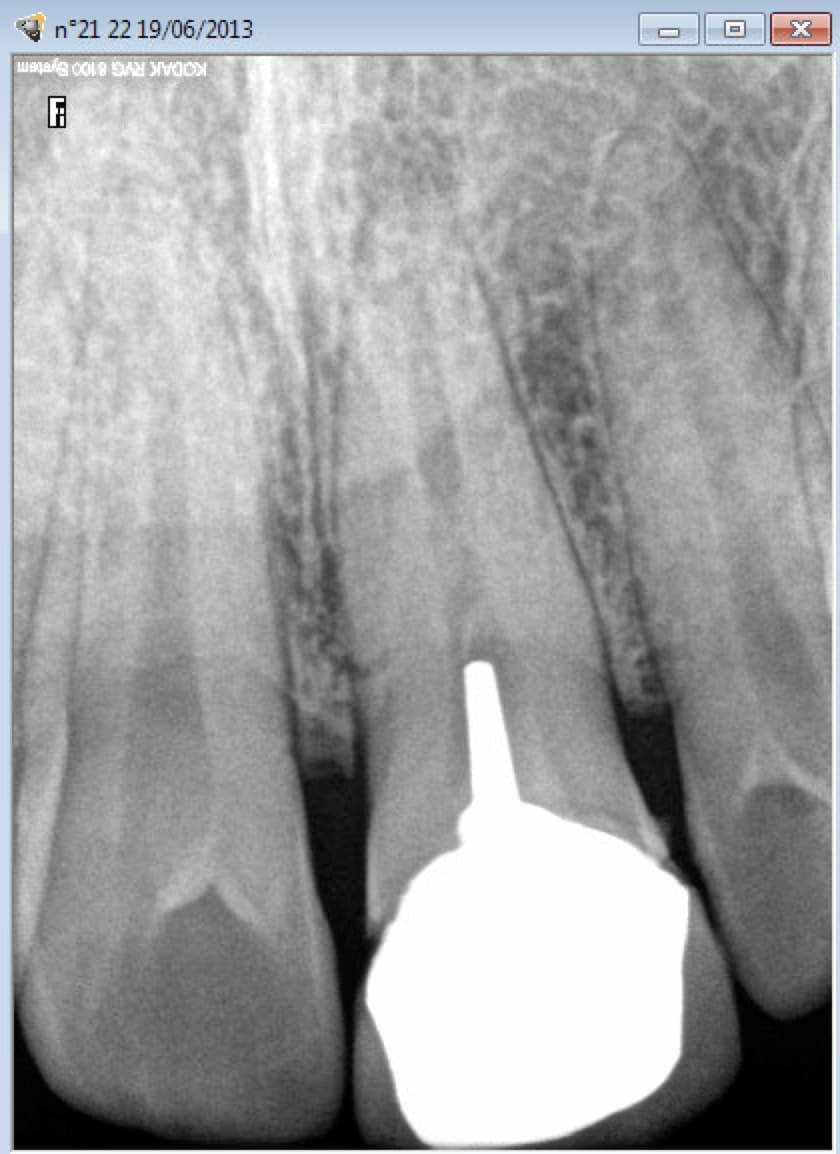

faux canal et injection d'hypo dans le péri apex..(d'après ce que je sais la dent est conservable et il y avait une hypoesthésie locale) j'ai pas reconnu les signes .. je les connaissais pas ....oui je sais c est dingue! pas de jugement svp, je me suffit à moi-même!!

non j'ai mis moins de 2ml en deux fois. le patient s est plaint mais je pensais avoir mal aspiré et que l'hypo avait fuité au niveau des muqueuses... j'ai pas reconnu les signes. le patient est parti avec une douleur , il n'était pas gonflé. je l'ai revu deux/trois h après gonflé et dl forte.. j'ai fait une rétro, j'ai rien vu... la dent était en PAA depuis au moins une semaine, je l'ai mise ss ATB (metro) en plus. Le jour même il est parti voir un confrère qui a diagnostiqué le faux canal. J'ai revu le patient car il voulait s'expliquer.J'ai l'impression qu'il croit que je lui ment, que je savais pour le faux canal alors que pas du tout. Je me suis excusée pour les complications . Donc j'ai merdé c'est clair, maintenant j'ai pas non plus envie de m'enfoncer.

c'est plus pour l'hypoesthésie qu'il risque de réclamer qqchose.